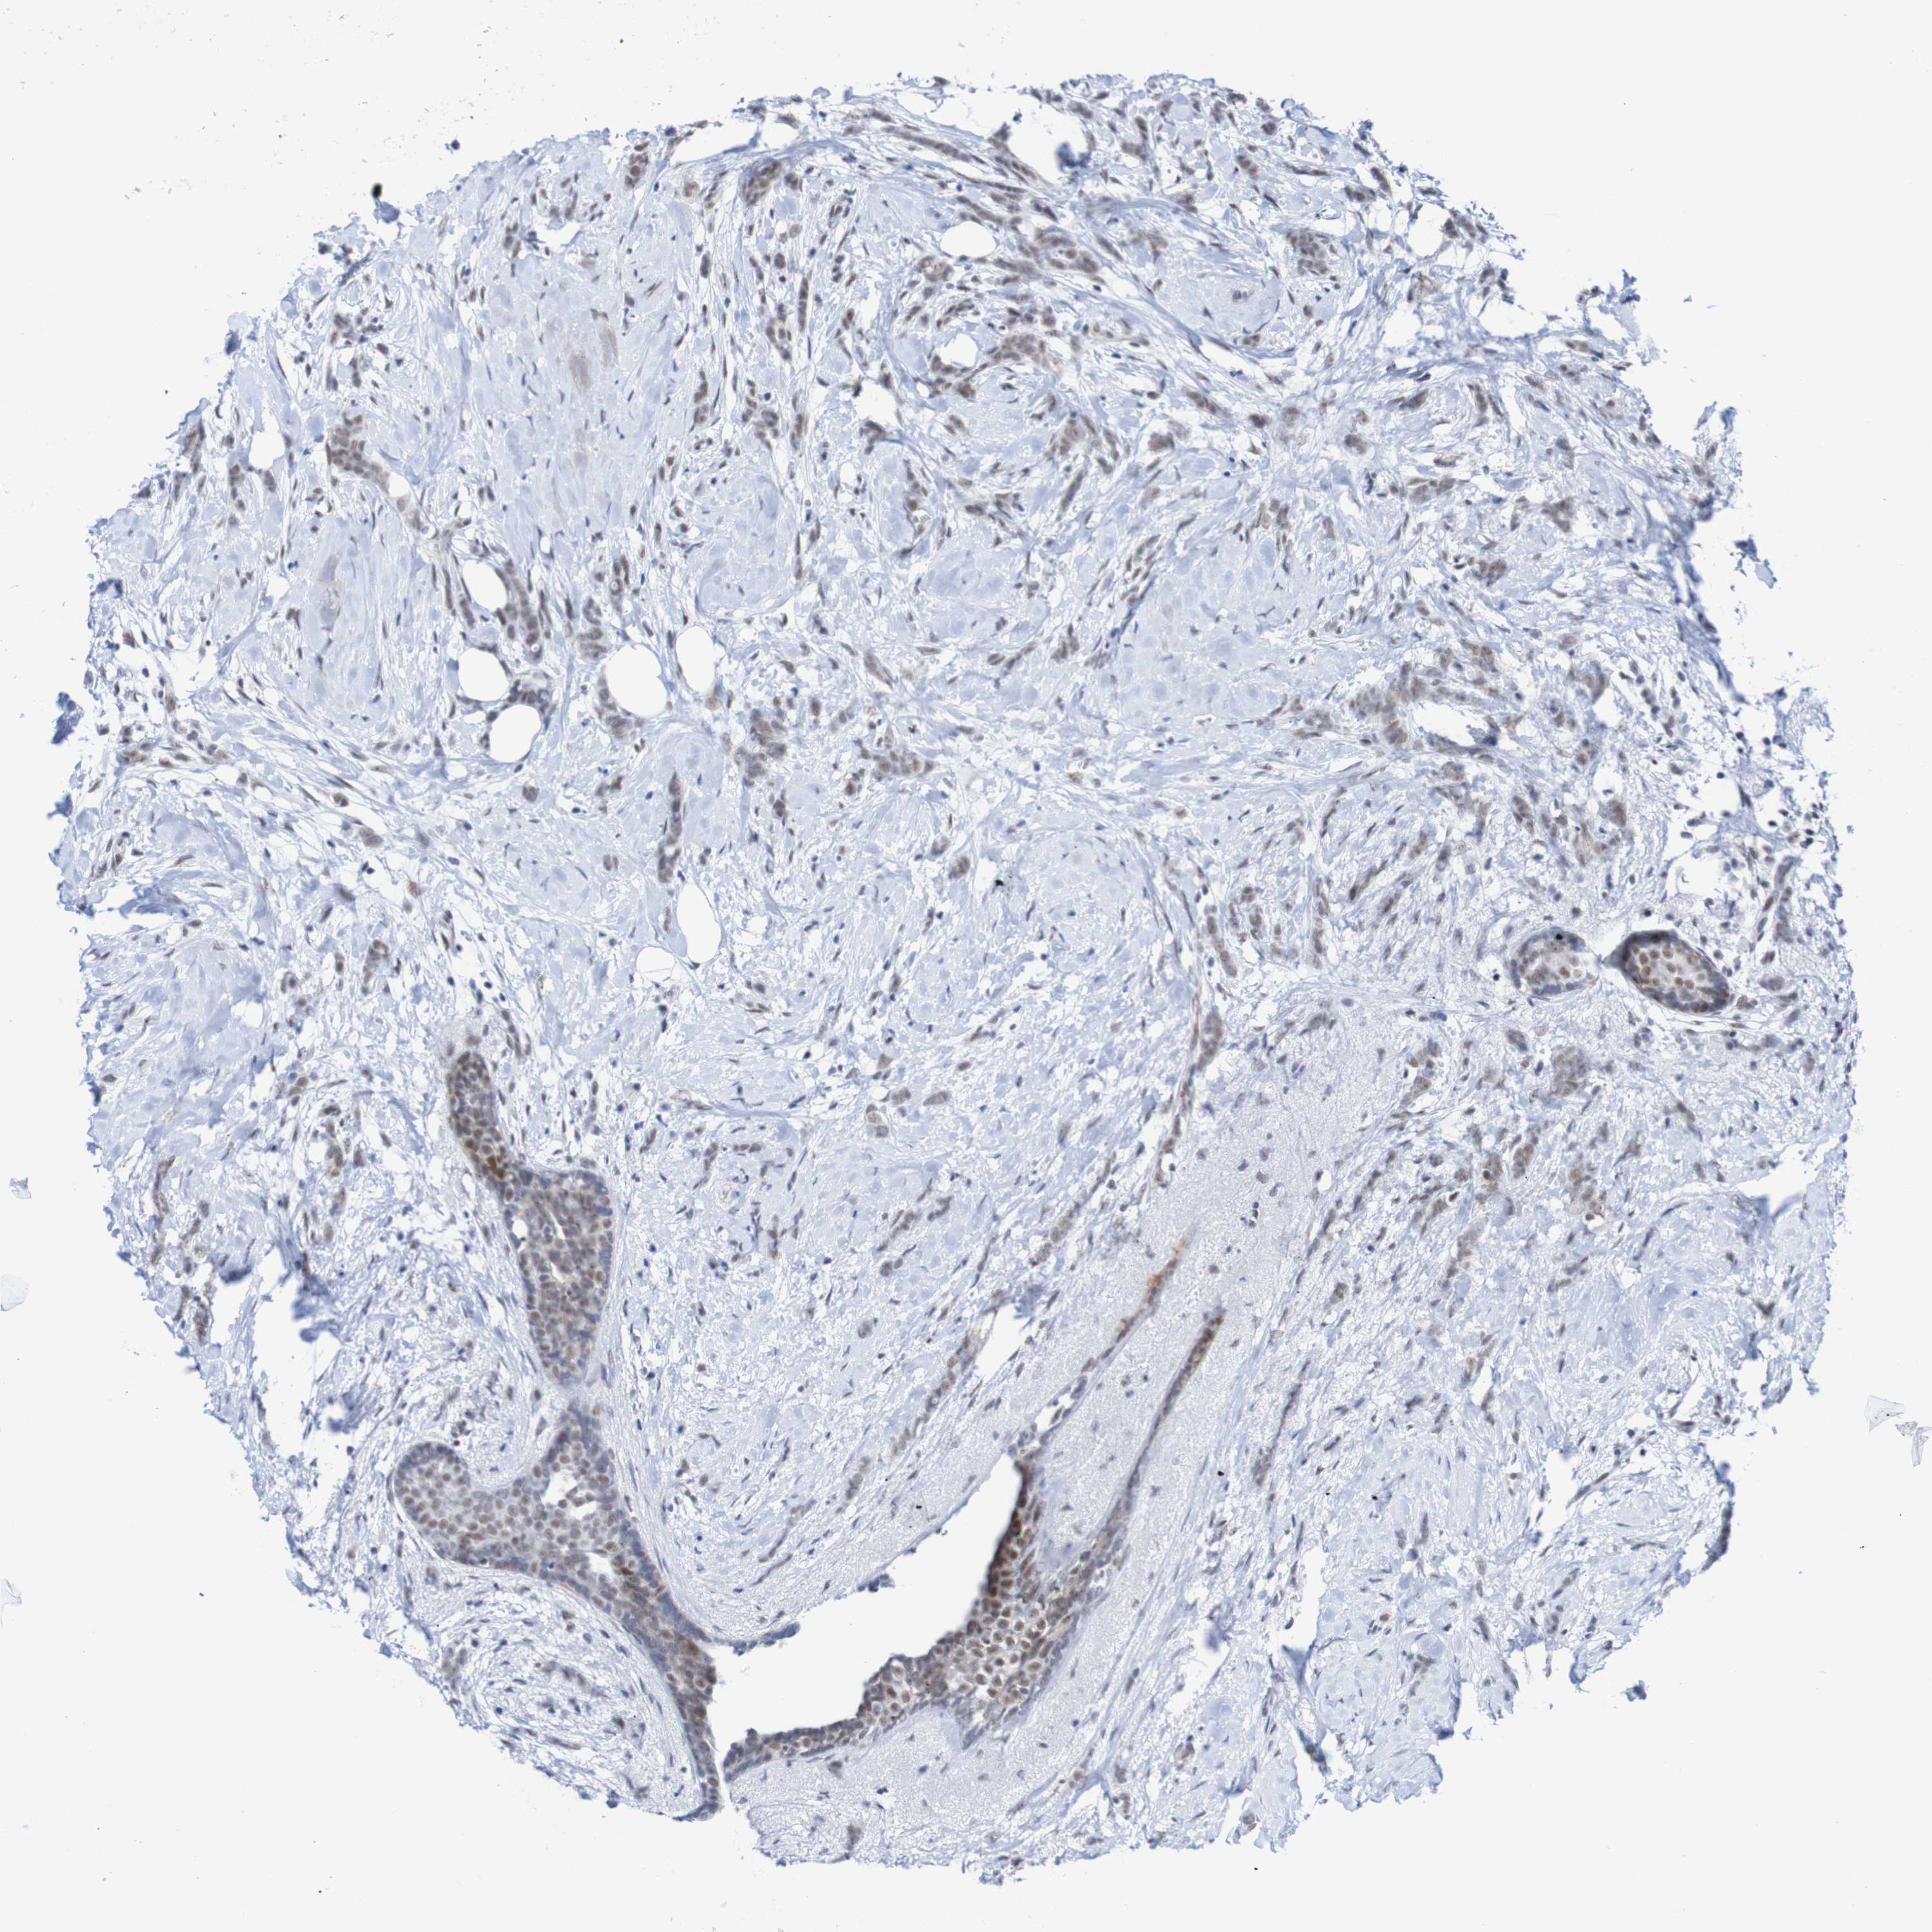

CANCER BREAST CANCER Show tissue menu

BRCA TCGA BRCA VALIDATION PROTEIN EXPRESSION